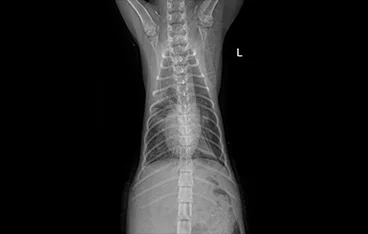

탈장(서혜부, 회음부, 횡격막 탈장)

탈장수복 (주변 조직, 의료용 mesh 등)

• 횡격막탈장

• 횡격막탈장 수술 전

횡격막탈장 수술 후